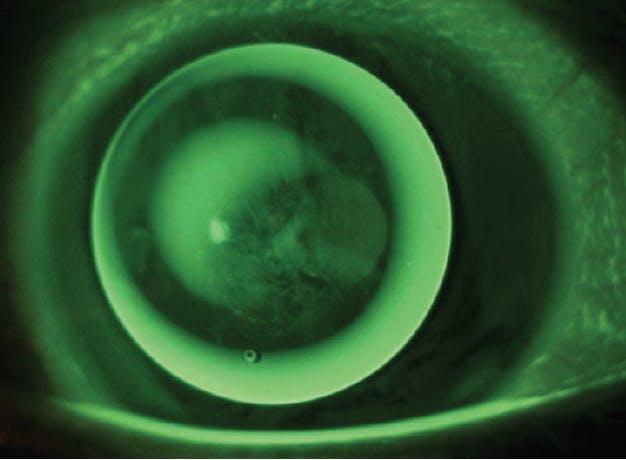

Figure. An image of advanced keratoconus requiring a medically necessary contact lens.

Photo courtesy of Melissa Barnett, OD, FAAO, FSLS, FBCLA.